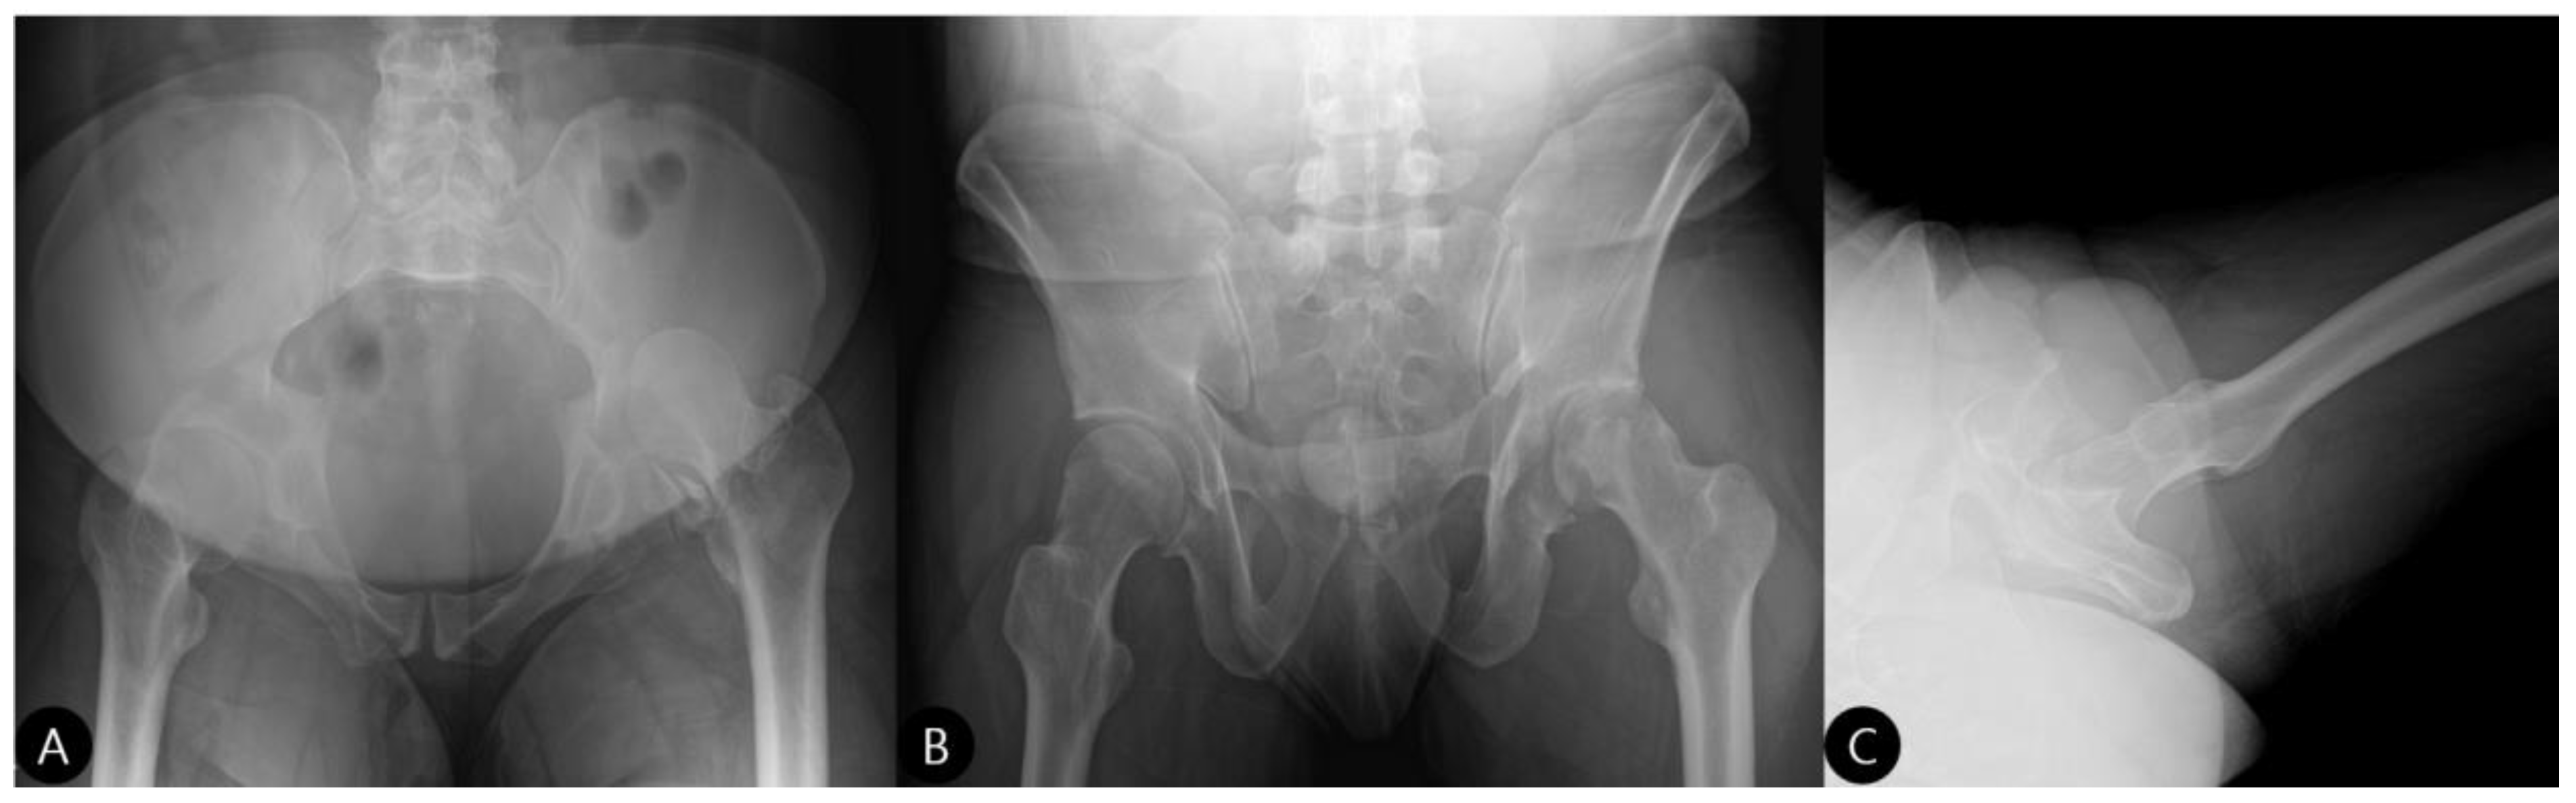

2.2. Preoperative Assessment

- Exposure and Assessment: The hip joint was exposed. The femoral head was found to be dislocated posteriorly. The posterior wall was severely comminuted into six small, non-viable osteochondral fragments (Figure 3), confirming the impossibility of anatomical reduction and stable fragment fixation.